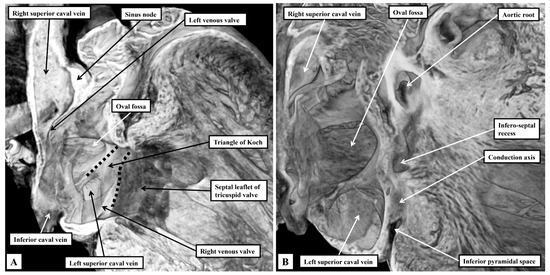

Background: Since the study of Lev and Thaemert in 1973, little has been published concerning the overall arrangement of the murine conduction tissues, in particular with relation to gross anatomical landmarks. We recently emphasised the potential va...